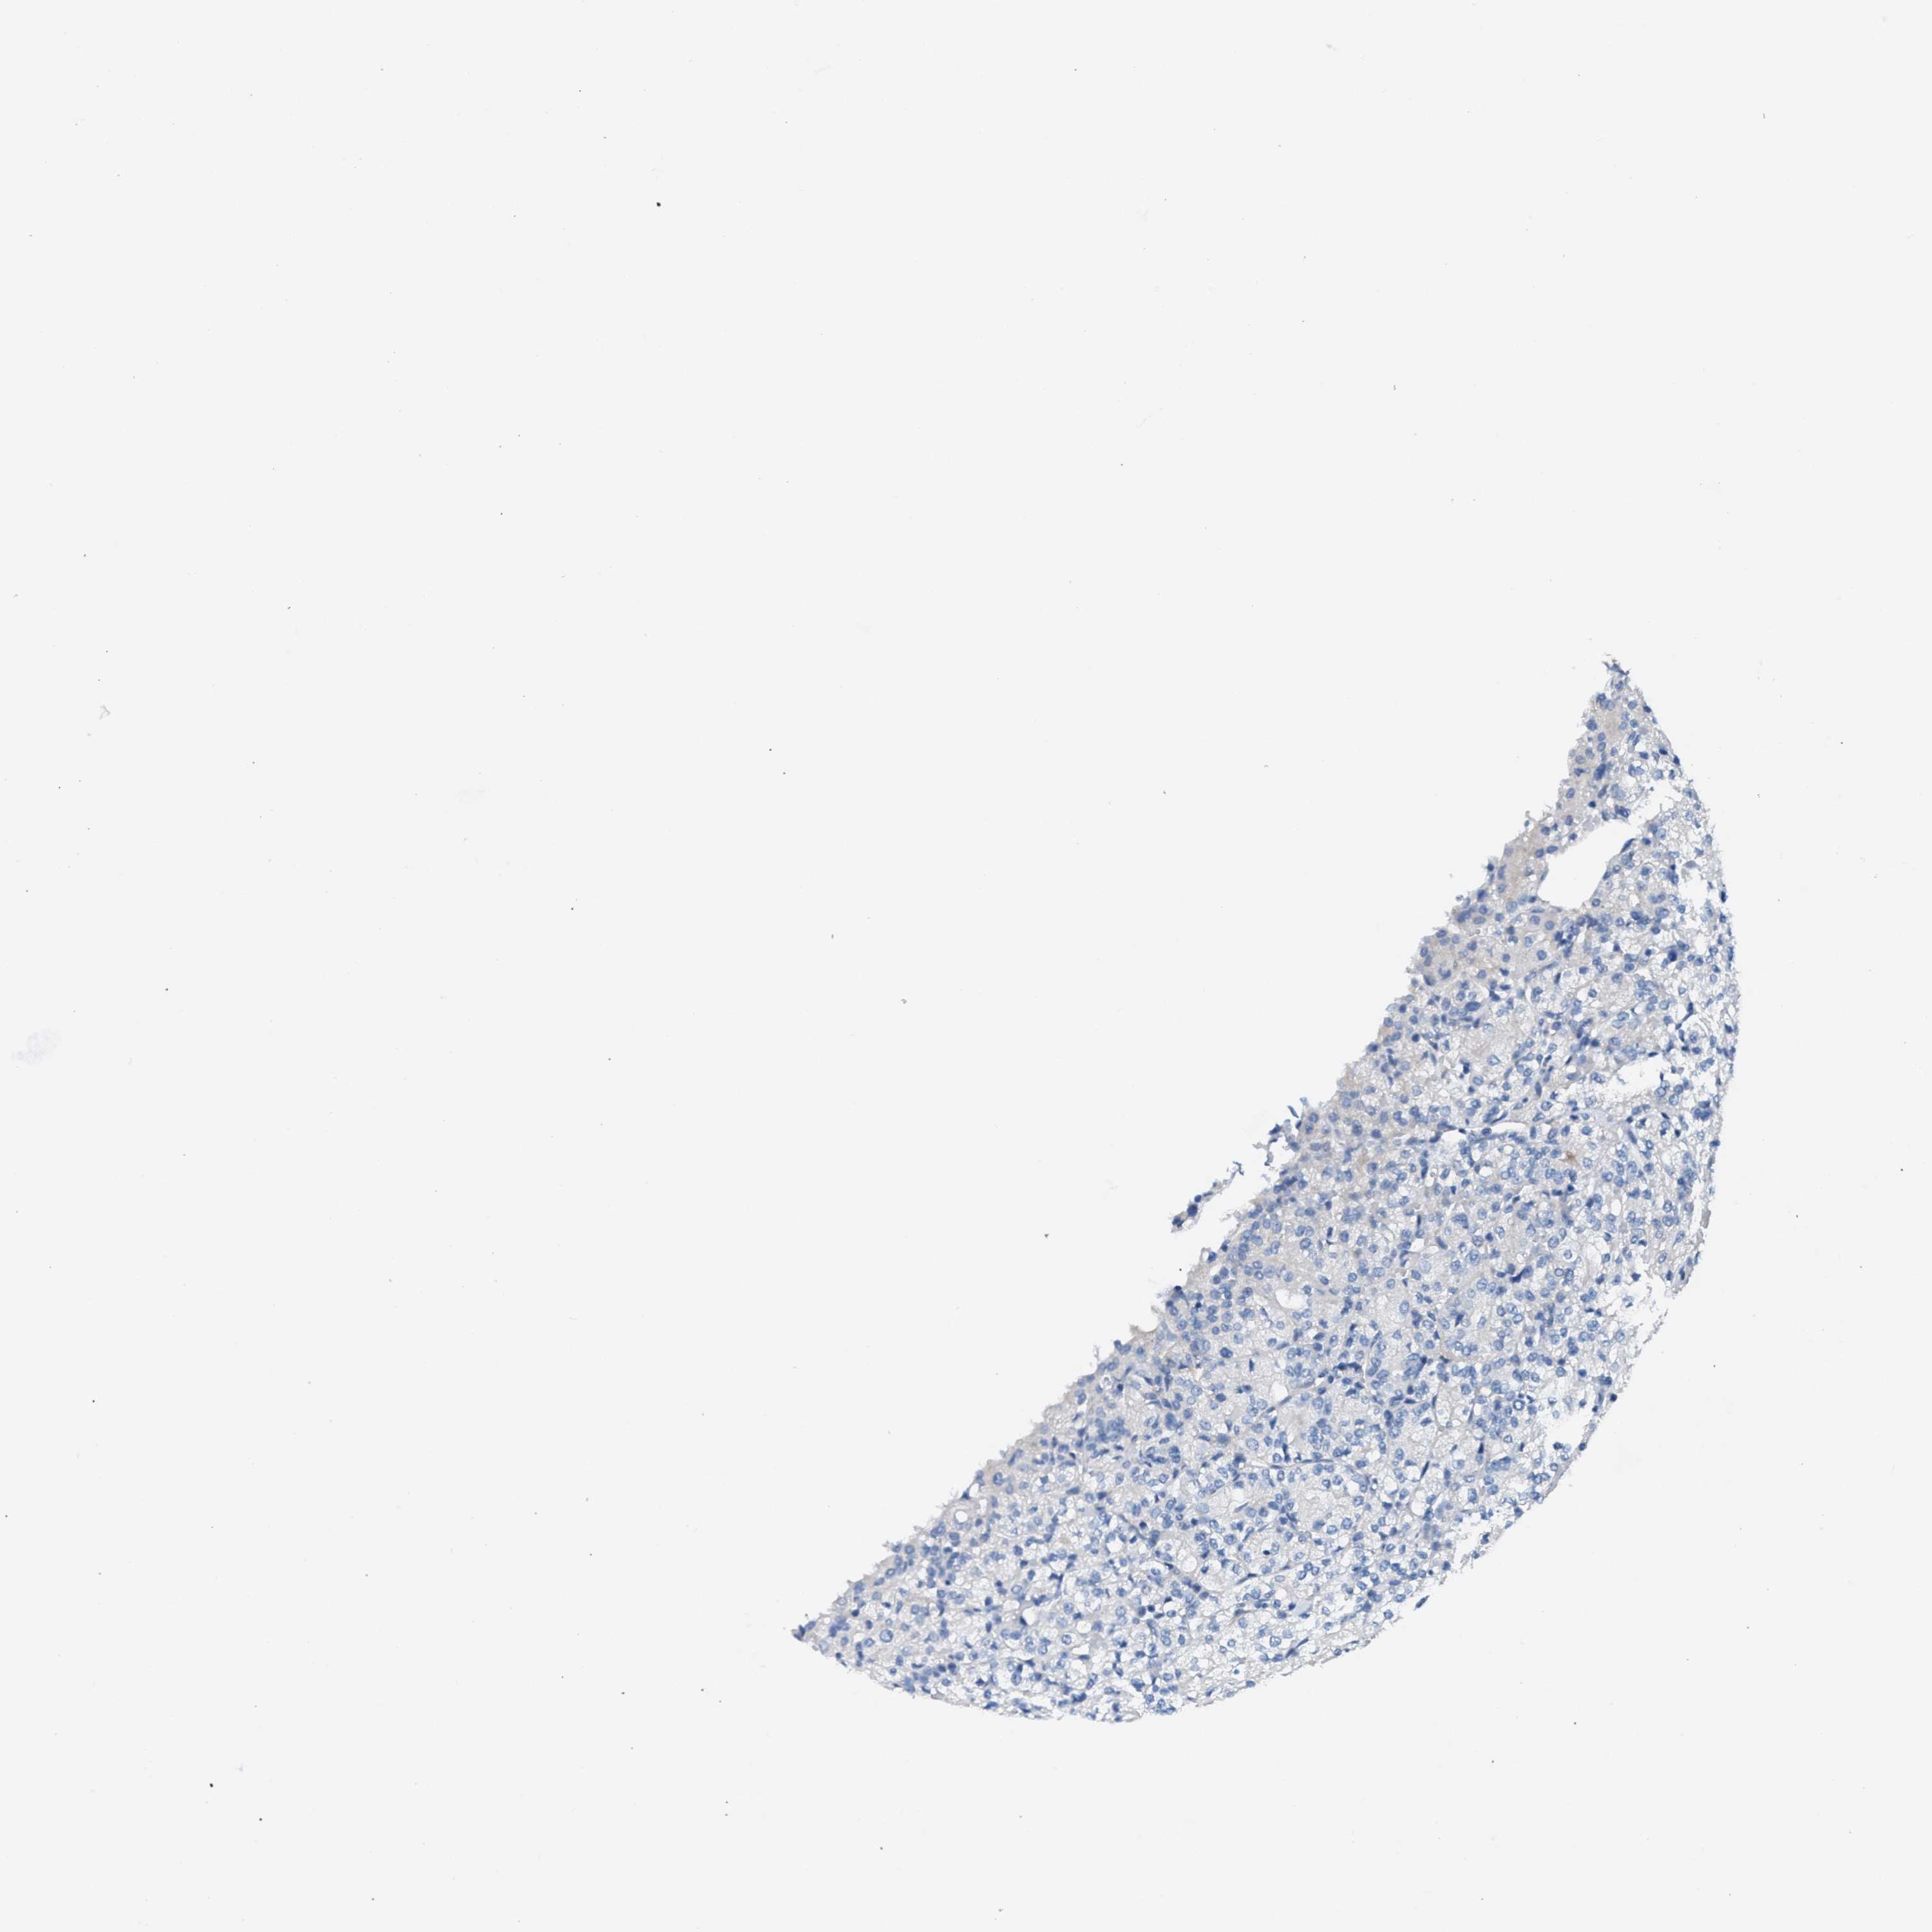

CANCER RENAL CANCER Show tissue menu

KICH TCGA KIRC TCGA KIRC VALIDATION KIRP TCGA PROTEIN RCC CPTAC PROTEIN EXPRESSION